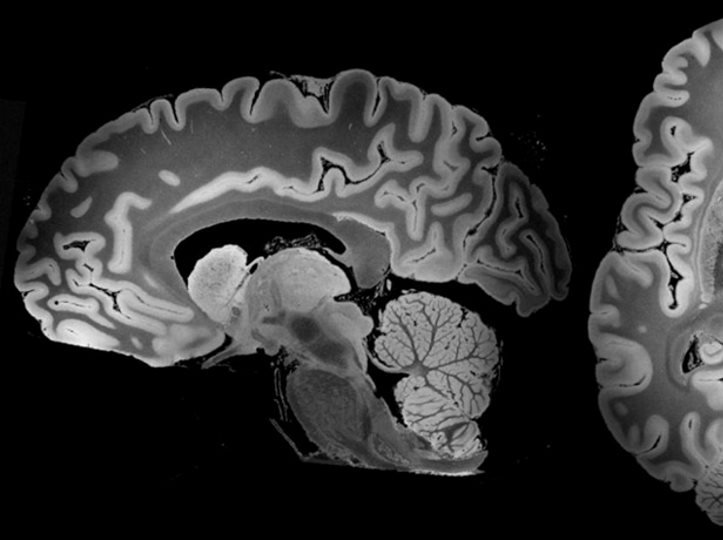

A 100-hour MRI scan captured the most detailed look yet at a whole human brain

Over 100 hours of scanning has yielded a 3-D picture of the whole human brain that’s more detailed than ever before. The new view, enabled by a powerful MRI, has the resolution potentially to spot objects that are smaller than 0.1 millimeters wide. “We haven’t seen an entire brain like this,” says electrical engineer Priti Balchandani […]